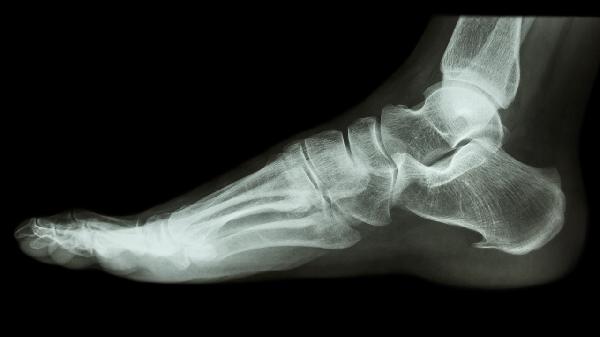

4、骨质疏松检测

X线骨密度测量是骨质疏松的常规筛查手段,通过观察骨小梁稀疏程度和椎体压缩变形等改变进行评估。腰椎和髋部是常用的检测部位,严重骨质疏松患者可见椎体双凹变形或楔形变。